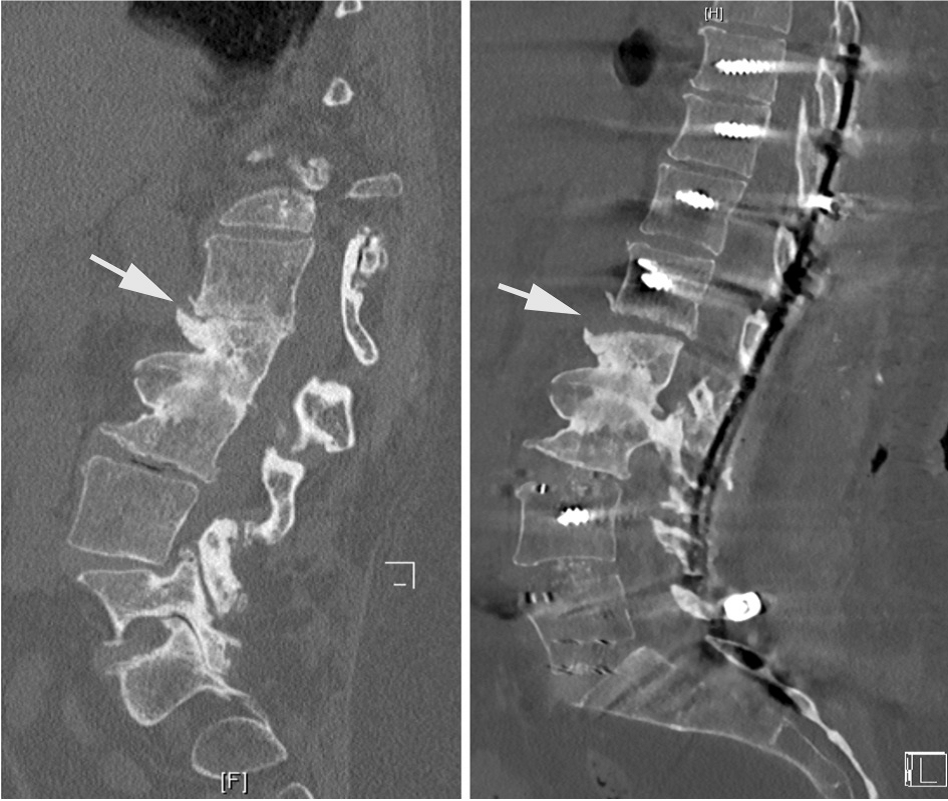

腰椎L3-4椎间融合联合后路经皮椎弓根钉内固定。1年随访时CT显示椎间骨性融合